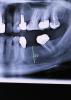

ВИТА Опубликовано 22 августа, 2012 Автор Поделиться Опубликовано 22 августа, 2012 ну вот посмотрите ещё пример у одного и того же пациента. с одной стороны сделала так Ссылка на комментарий

DShu Опубликовано 23 августа, 2012 Поделиться Опубликовано 23 августа, 2012 с другой стороны - такВ области мезиального импланта расщепление вижу, у дистального нет. Если бы там было расщепление, имплант бы полностью был окружен своей костью, а у вас вестибулярка все равно оголена получилась.И я все таки сторонник фиксировать мембрану, чтобы обеспечить полную иммобилизацию материала. В вашем случае есть риск его сползания.Я бы сделал тут однозначно блок, или импланты+биоос+цитопласт (или титановая мембрана) Ссылка на комментарий

carloss Опубликовано 23 августа, 2012 Поделиться Опубликовано 23 августа, 2012 (изменено) Тоже поддержку что расщепления здесь и не было.Ситуация еще хуже чем в теме "расщепление по карлосу" которое представил биер.Не хватает горизонтального пропила внизу что как раз и дало бы почву для сплита. Опять же вы просто вписали эти имплантаты в то что было и сверху просыпались.Блоков не нужно бояться. Если их делать много и часто то результат вас будет так радовать, что расщепление вам делать уже не захочется. Без обид. http://s61.radikal.ru/i173/1208/96/e3adbd23dfeb.jpg http://s017.radikal.ru/i410/1208/ce/edab2b6855d4.jpg толщина кости вестибулярно в области 35, на фотке с дыркой от 2-х мм пилота и с имплантом одинакова.. соответственно расщепление произошло.. при том, что не было не только нижнего горизонтального, но и вертикальных распилов http://s017.radikal.ru/i443/1208/71/10d1b9973b69.jpgно в любом случае под мембрану(опять же 2 слоя) обязательно аутокость + биоосс для большего объёма.. это мой протокол http://s017.radikal.ru/i425/1208/e3/a95a0270afe4.jpg да.. 34 медиальная консоль)) Изменено 23 августа, 2012 пользователем carloss 1 Ссылка на комментарий